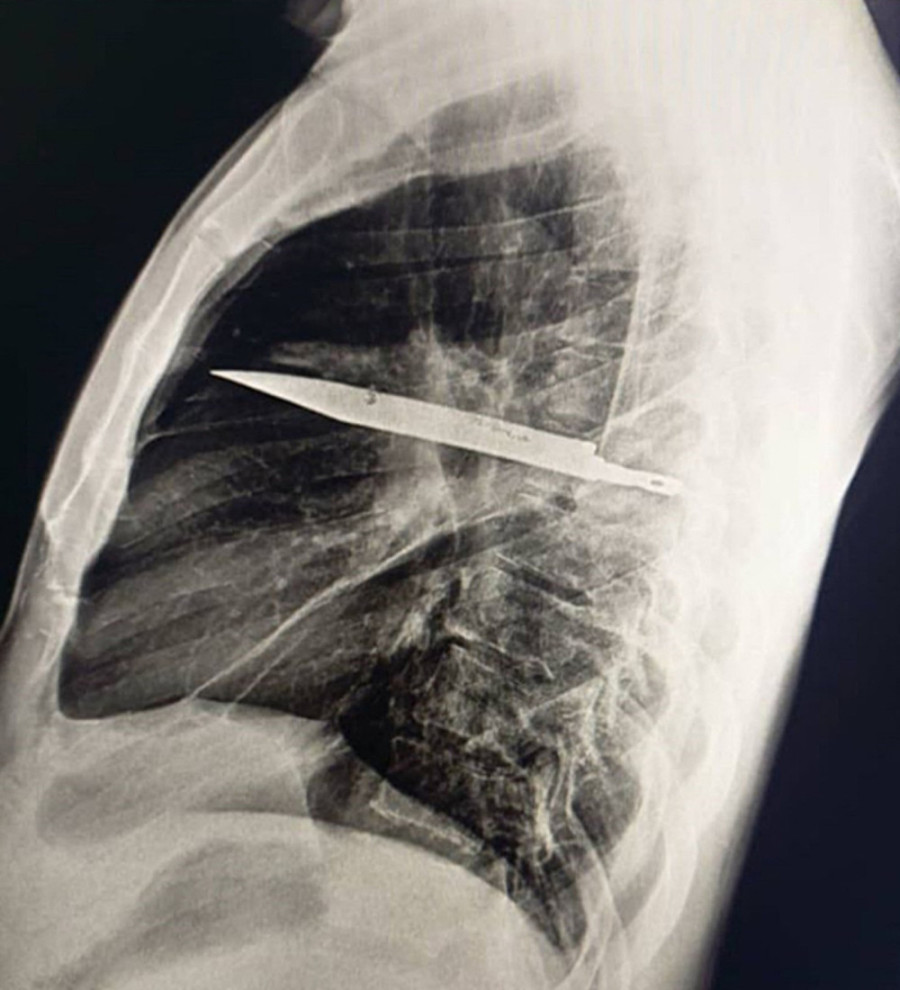

Pacijent je izgledao sasvim zdravo - nije imao bolove u grudima, niti probleme sa disanjem ili kašljem. Uprkos tome, lekari su odlučili da urade rendgen, a rezultat ih je šokirao. Na snimku se jasno video veliki metalni predmet - nož koji je u njegovim grudima stajao čitavih osam godina.

Kada su ga suočili sa nalazom, čovek se prisetio da je pre gotovo deceniju bio teško povređen u jednoj tuči, kada je zadobio brojne posekotine na licu, leđima i grudima. Kako živi u udaljenom području, tada je primio samo površnu medicinsku pomoć, bez rendgenskog snimanja. Tako je smrtonosni predmet ostao u njegovom telu, potpuno neprimećen.

Lekari su zaključili da je organizam na neverovatan način obavio strano telo zaštitnim tkivom, zbog čega čovek nije imao ozbiljne simptome. Tek kada je počeo da curi gnoj, bilo je jasno da kapsula popušta i da počinju komplikacije koje su mogle biti fatalne.

S obzirom na rizik, odmah je zakazana operacija. Nož je izvađen zajedno sa oštećenim tkivom, a oporavak je prošao iznenađujuće brzo. Već deset dana kasnije pacijent je otpušten iz bolnice - živ i zdrav, iako je u sebi godinama nosio smrtonosan predmet. Lekari su naglasili da je reč o neverovatnoj sreći i slučaju koji podseća koliko je važno ozbiljno shvatiti povrede.